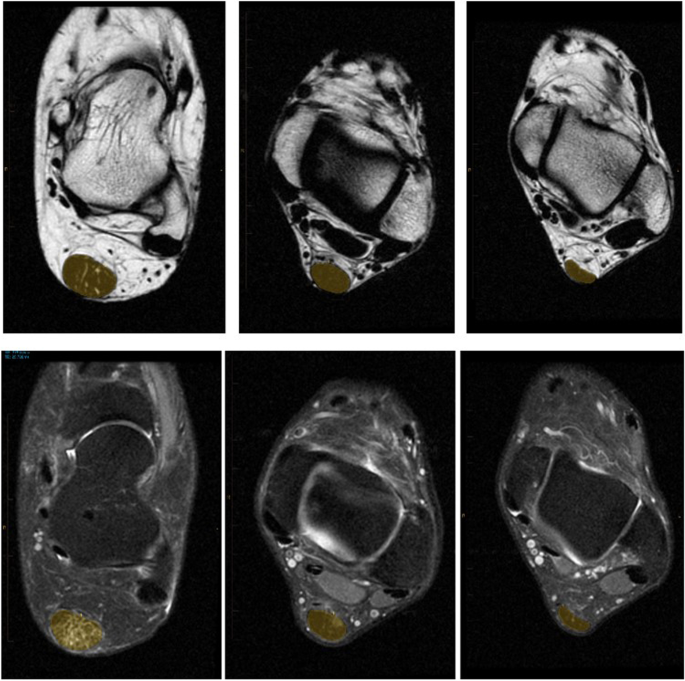

Each Dixon scan generated a DICOM file with 34 transverse slices each for four image series (in-phase, opposed-phase, lipid-only, and water-only). We used Inteleviewer (version 4–12-1-P451, Intelerad Medical Systems, Canada) to simultaneously view the four transverse image series, alongside a fifth sagittal-view window for orientation purposes. The calcaneal and gastrocnemius insertions were landmarked on the sagittal scan, and then the three transverse Achilles tendon scans which were closest to the midpoint of the Achilles tendon (i.e. midway between the two landmarks) were manually contoured, noting their distance from the calcaneus. This location of the tendon was chosen for analysis a priori as being the most common location for Achilles tendon pathology to occur. Next, lipid and water signal were range normalized for each tendon by contouring three consecutive slices of the Kager fat triangle and flexor hallicus longus muscle, and dividing the corresponding tendon fat and water signals by the resulting values. The normalization values were equivalent across the three groups for both fat (ATX 2689(497); ATY 2648(370); ATN 2713(375) and water (ATX 1268(261); ATY 1353(170); ATN 1336(188). The average Achilles tendon lipid and water signals in the contoured areas of the Achilles tendon (relative to the normalized signal) were then calculated, as per Griffith et al. [15] and multiplied by their cross-sectional area. Examples of contouring on the fat and water images are shown in Fig. 1. This yielded three data points, in arbitrary units, for each of Achilles tendon fat and water content (one from each evaluated transverse slice), which were averaged to yield a single value. Finally, the maximal anterior–posterior (A-P) thickness for each tendon was also recorded.

Lipid (top) and water-only (bottom) Dixon method transverse MRI of ATX (left), ATY (middle), and ATN (right) participants’ left ankle with Achilles tendon contouring shown in yellow. High signal (in white) indicates significant fat and water infiltration in the ATX patient image. A small area of water infiltration is seen in the ATY tendon, but with no corresponding fat signal. Anterior–posterior thickening is apparent in the ATX and ATY tendons